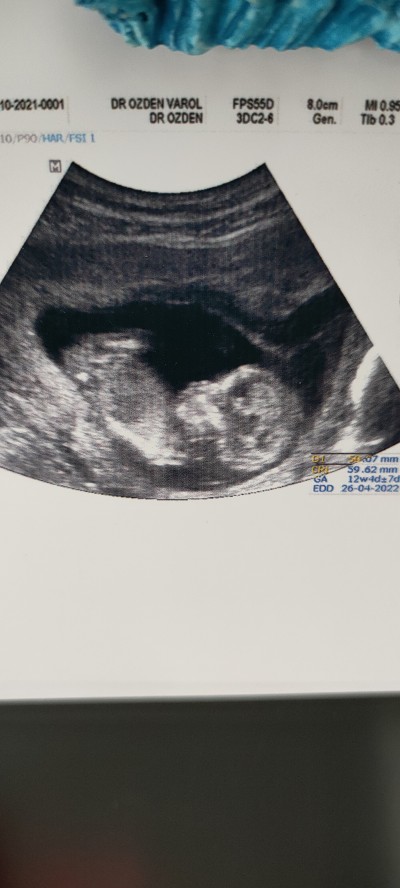

Merhaba cinsiyetini tahmin edebilecek biri var mı?

buda bnmki oğlumda sennki gibiydi 2.ciye hamileym dün gittik arkasına döndü kndini gostrmedi doktor baskı yaptı karnma öyle döndü snra bakti kordon var ogrenemedk senn kaç haftalk

Burda 13 haftalık şuan 15 oldu bakalım:)